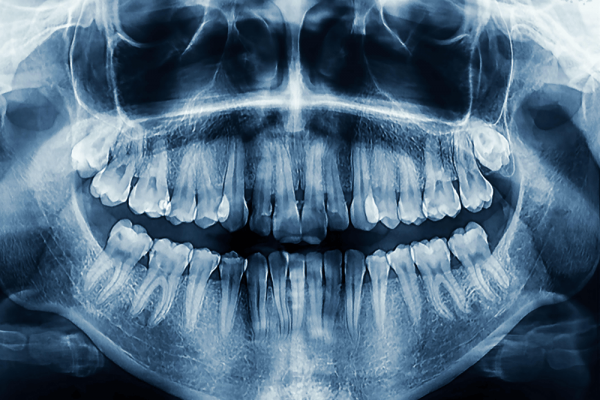

Several days ago, I spent more than I would have liked on a dental procedure that involved removing decay from one of my molars, doing a lot of horrible-sounding drilling and scraping, then saving the delicate bits that remained by capping it with a fake tooth. My dentist insisted this was called a “crown,” but I know a euphemism when I see one.